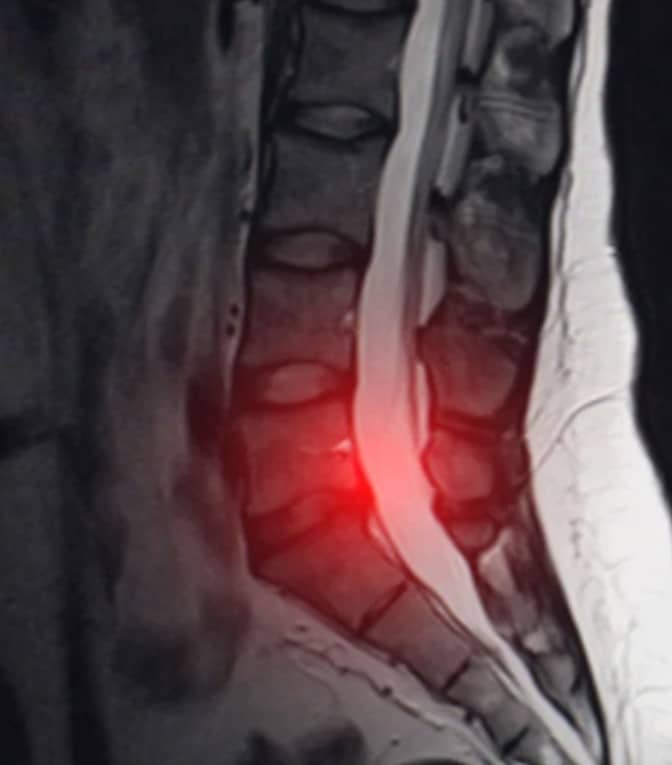

Una hernia lumbar ocurre cuando uno de los discos intervertebrales de la zona baja de la columna se desplaza o se rompe, presionando los nervios cercanos. Aunque esta condición puede desarrollarse gradualmente, muchas personas no la identifican a tiempo porque los síntomas iniciales pueden parecer menores o confundirse con dolores musculares comunes.

En Imatecsalud, contamos con una herramienta clave para diagnosticar hernias lumbares con precisión: la resonancia magnética (RM). Este examen no invasivo ofrece imágenes detalladas de los discos intervertebrales, nervios y estructuras cercanas, permitiendo a los especialistas identificar el grado de afectación y planificar el tratamiento adecuado.

Ventajas de la resonancia magnética para diagnosticar hernia lumbar:

- No utiliza radiación.

- Es indolora y segura.

- Proporciona imágenes claras y detalladas.

- Permite detectar otras posibles causas del dolor.